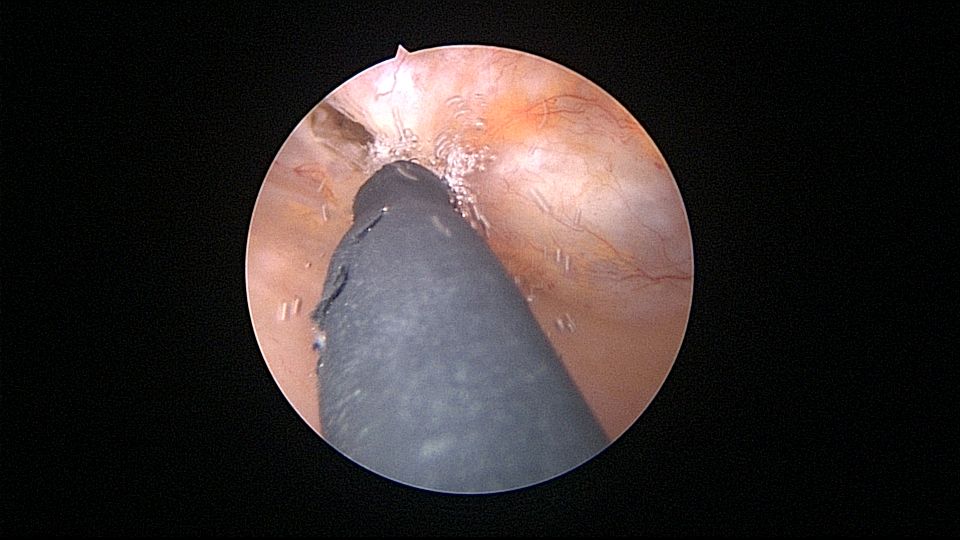

患者69岁,G2P1,顺产1次。产后曾安环1次,后自然脱落,再次安环距今40年,绝经20+年。外院取环失败(没有进入宫腔)。B超子宫后位,宫内O型环距宫底0.3cm,宫腔积液(按以往经验,考虑宫腔积脓),另见宫内稍强回声1.1cm*0.8cm。子宫极度后倾后屈位,宫颈管狭小坚硬,扩张困难,宫腔镜难以进入。宫腔镜直视下充盈膀胱,B超监护下异物钳指示宫腔方向,宫腔镜艰难进入宫腔,见灰白色脓液涌出,O型环位置正常,宫腔后壁占位包块位于节育环圈内,约1.5cm*1.5cm*1cm,异物钳顺利取出节育环。单极电针切除占位包块,但包块直径大于宫颈内口直径,异物钳多次尝试取出,均失败,不得已用单极电针切开宫颈内口左侧狭窄处,异物钳缓慢牵拉取出标本,膨宫液冲洗宫腔脓液,宫腔无其他异常。包块病检为内膜息肉。